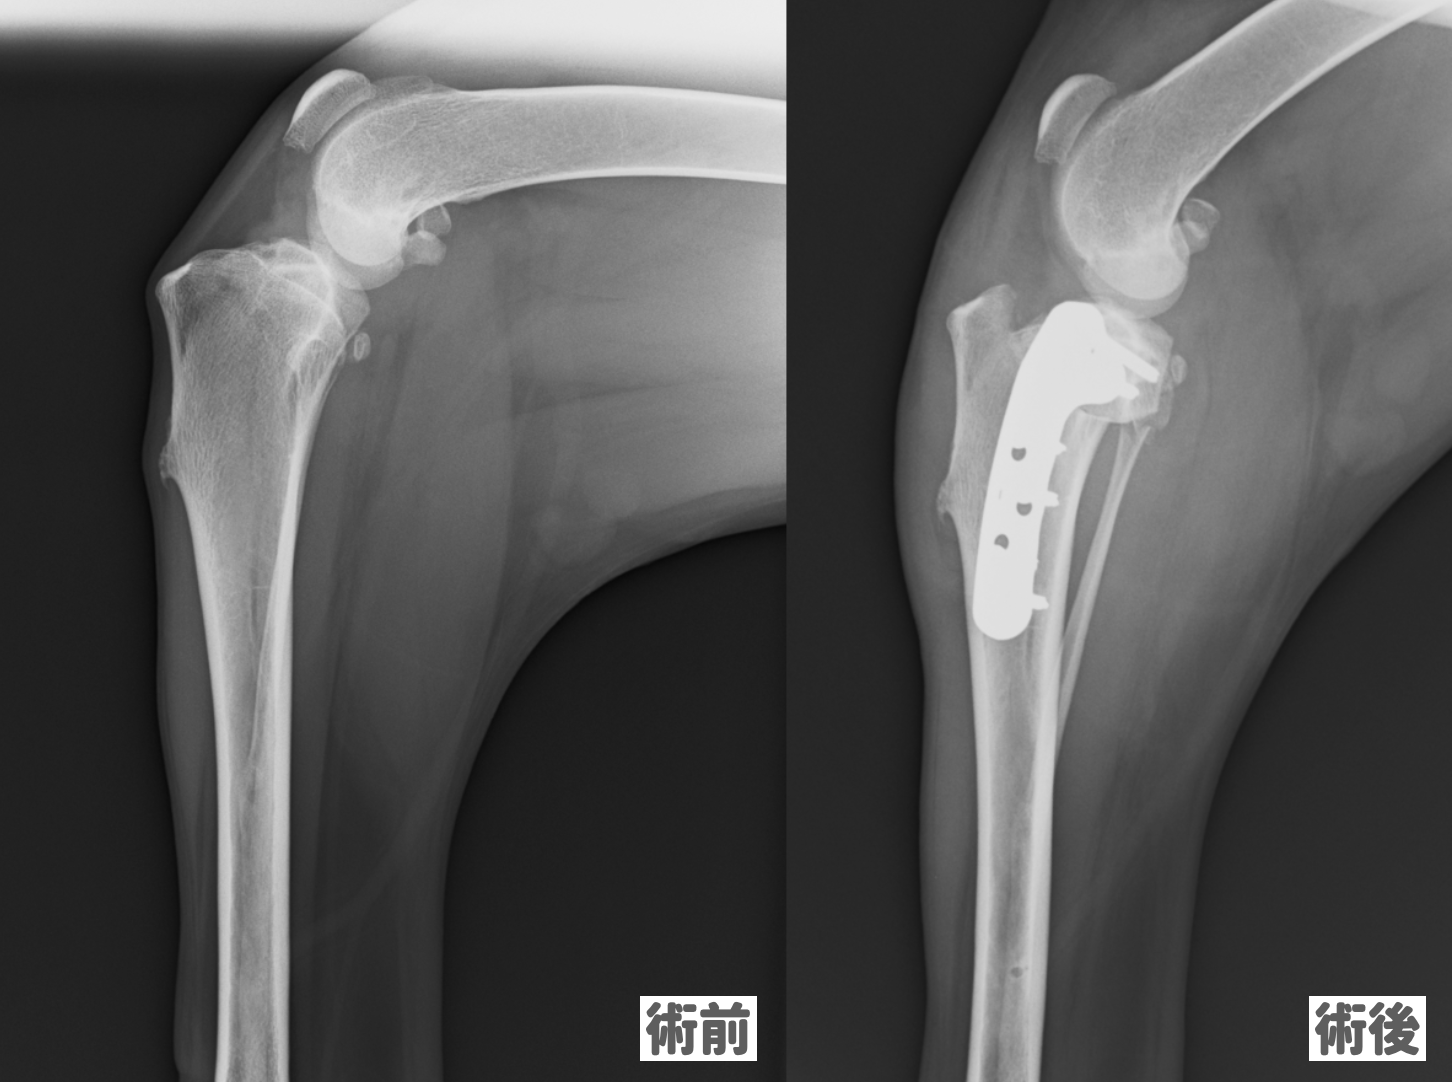

カッターで裁断したものなので、綺麗な裁断ではありません。問題なくスキャンできました。インターズー エデュワードプレス犬の前十字靱帯学治療を極めるための40章編者 PETER MUIR 監訳 泉澤 康晴310項定価 27500円(税込み)Ⅰ部 形態と機能1 十字靭帯の形態と機能2 十字靭帯の生体力学3 十字靭帯のリモデリングと修復4 半月の構造と機能5 正常およびCrCL欠損膝関節の生体力学Ⅱ部 十字靭帯断裂の疾病原因論6 前十字靭帯断裂の組織学7 前十字靭帯損傷の遺伝学8 十字靱帯の基質代謝と緩みの進行9 膝関節の形態学10 十字靭帯の変性における一酸化窒素合成と蛋白分解酵素活性の役割11 Ⅰ、Ⅱ型コラーゲン抗体の役割12 滑膜炎と膝関節の不安定性,どちらが先か?13 滑膜炎における滑膜の免疫応答の役割Ⅲ部 臨床的特徴14 前十字靭帯断裂の疫学15 十字靭帯断裂の既往歴および臨床症状16 前十字靭帯の部分および完全断裂17 後十字靭帯断裂18 膝関節のストレスX 線検査19 膝関節における超音波検査20 膝関節のコンピューター断層撮影法21 膝関節の磁気共鳴断層像Ⅳ部 手術による治療22 外科治療における関節鏡 vs.関節切開23 関節洗浄24 関節外安定化25 脛骨高平部水平化骨切り術26 脛骨粗面前進化術27 関節内法28 脛骨骨切り術を受けた前十字靭帯に障害のある膝関節の生体力学29 膝関節の安定化手術後の関節鏡によるフォローアップ検査30 前十字靱帯の辺縁切除31 前十字靱帯断裂と同時に発生する半月損傷の外科的治療32 半月解放術33 膝関節安定後における関節炎の進行34 膝関節安定術後に残存する跛行Ⅴ部 十字靭帯断裂を発症した犬の内科的管理35 膝関節炎の内科的治療36 前十字靭帯断裂を発症した犬におけるリハビリテーションⅥ部 将来の方向性37 飼い主に限定した結果の測定38 犬の人工膝関節全置換術39 再生医療と前十字靱帯の修復40 疾患修飾療法書き込み等確認しておりますが確認漏れや、一度人の手に渡った商品であることをご理解の上でご購入よろしくお願いいたします。匿名配送獣医臨床小動物動物病院動物看護ペット